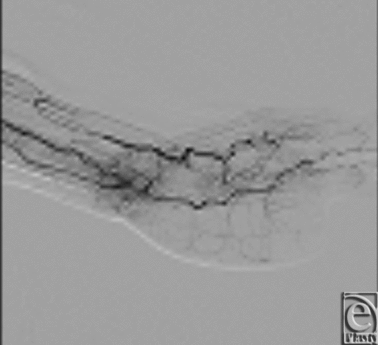

At 6 months follow-up, the patient had recovered increased range of motion of the remaining fingers of her left hand (Figs 7 and 8). The patient reported she had returned to all her previous activities including the ability to play tennis. Angiographic evaluation demonstrated a patent-reconstructed superficial palmer arch of the left hand, with patency of the flow-through ALT flap vessel (Fig 9).

![]() |

| Figure 9. Postoperative angiogram at 6 months, which demonstrates a patent reconstructed superficial palmer arch of the left hand with patency of the flow-through anterolateral thigh flap vessel. |